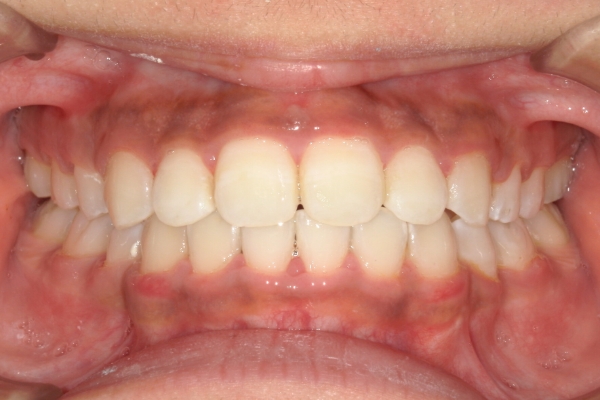

BEFORE

治療前

AFTER

治療後

上顎前歯が1cm近く前方に出ており、叢生を改善しつつ前歯を大きく引っ込めるために上下顎小臼歯の抜歯が必要と診断しました。治療後は、主訴であった前歯の突出と奥歯の噛み合わせのずれが改善され、上下の咬合関係が安定しました。